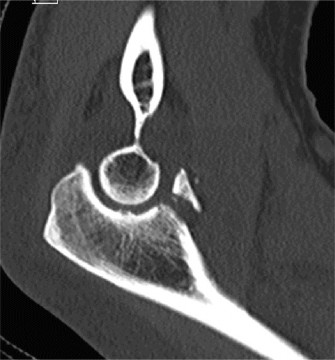

A sophomore, high school wide receiver presents to your clinic at the beginning of his football season. He reports a dislocation event after being tackled; his shoulder was “put back in place” by the on-field athletic trainer. A CT scan taken in the hospital today is shown (Fig. 2–33). He has been recruited by numerous colleges, plans to play at a division 1 school, and is very eager to return to the field.

Figure 2–33

What is the best treatment option for this patient?

Discussion

The correct answer is (E). A large bony fragment (>20%) makes the failure rate with nonoperative treatment (Answers A, B) unacceptably high. This question is meant to illustrate the challenges associated with treating an in-season athlete and highlighting the indications for surgery after a first time dislocation event. Typically, early in a season, providers will initiate an aggressive PT program and try and return athletes to the field within a few weeks so that they can play out the remainder of the season. Towards the end of the season, when there is insufficient time to rehab a patient, one may choose early surgery so that the patient has maximal time to recover prior to the next season. In this case, even though the

patient is extremely motivated to return to the field and has only sustained a single dislocation event, the large bony Bankart lesion behooves surgical treatment. The best option for him would be to have early surgery and have a maximal amount of time to prepare for his senior season. A Latarjet procedure (Answer C) is used for patients with recurrent anterior instability and significant glenoid bone loss, and the Magnuson–Stack procedure (Answer D) is a largely historic procedure that was used for recurrent anterior instability. Objectives: Did you learn...? The common presentation of a patient with shoulder instability?